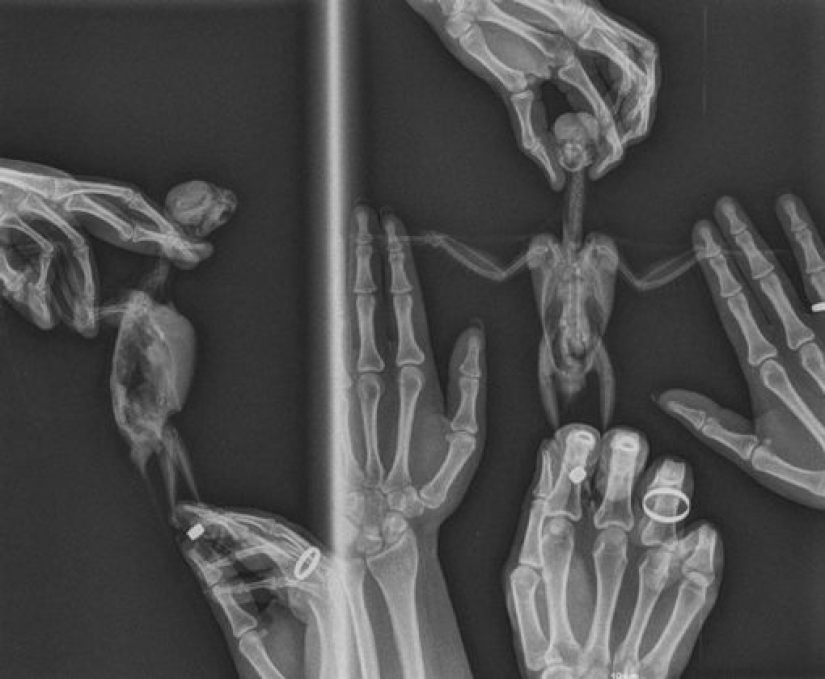

1. “This is how a parrot is x-rayed. The bird is alive and well. The procedure was done by a veterinarian and we were there to help keep our pet.”

3. "So my patient wouldn't let me x-ray her if I DO NOT PROMISE to x-ray her pony after..."

7. "My piercing is x-rayed."

8. "We made a beautiful Halloween card."

10. "Triple tongue piercing on my x-ray."

14. "My first x-ray on the second day at radiology school."